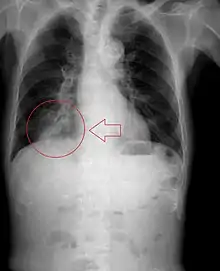

![]() | |

| Upper gastrointestinal series at the level of the esophagus, showing pulmonary aspiration of the radiocontrast agent | |